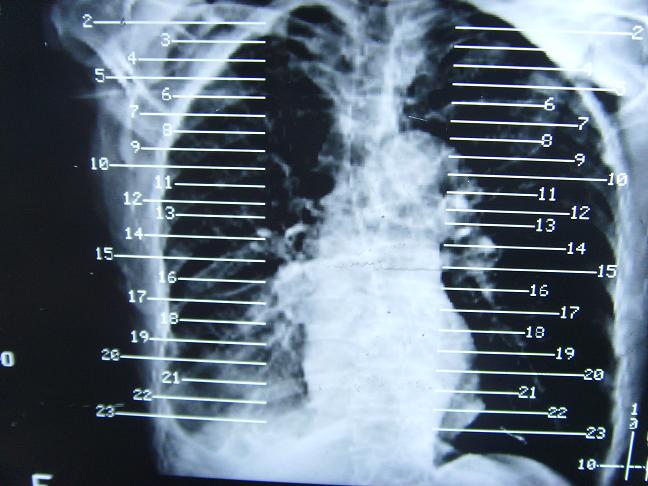

考虑  右肺新生物伴右下肺阻塞性肺炎,肺不张.右侧胸腔积液

考虑:右侧中心型肺癌伴下肺肺不张。

1)右肺中央型肺癌伴右肺下叶肺不张。2)慢性支气管炎,肺气肿。3)右侧胸腔积液。

1)右肺中央型肺癌伴右肺下叶肺不张。2)慢性支气管炎,肺气肿。3)右侧胸腔积液

右肺中央型肺癌伴右肺下叶肺不张。慢支肺气肿。右侧胸腔积液。